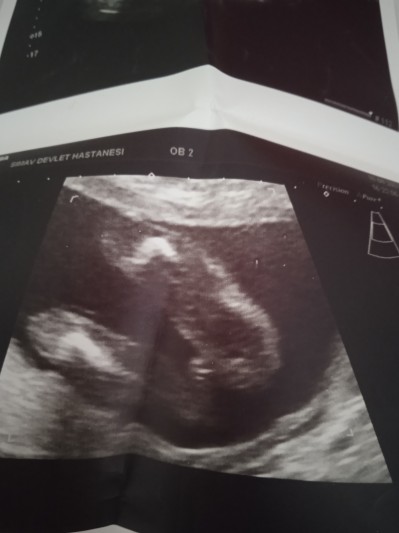

Kızlar 24 haftadayım ama bir türlü bebeğimin cinsiyetini tam bilen çıkmadı biri diyor kız biri erkek hayırlısı olsun Rabbim sağlıkla hepimizin bebeğini kucağına aldırmayı nasip etsin ama insan merak ediyor bu ikinci gebeliğim ilk kızımda böyle şey başıma gelmedi birde siz bakarmisiniz

Gebelik haftası 24+1

Erkek gibi sanki ama cokta cikik deil gibi benim 16 haftada gittimde ogrendim cok belli mesela ayni resim pozisyonda hayirlisi olsun canim hakkinda insallah erkektir ama karar veremedim vende tam

Bana kız gibi geldi. Erkekte daha fazla çıkıntı oluyor. 24 hafta bayağı büyümüş daha net belli olurdu erkek olsaydı. Kızlardada çıkıntı olabiliyormuş. Hayırlısı olsun inşallah

Erkek kesin çünkü ilk bebismin cinsiyeti de böyleydi erkek cikti

Kuzum sanki kız gibi duruyor kesesi ya Bi arkadaşımında tam böyleydi 28 haftaya kadar göstermedi bigun nasıl olduysa Göstermiş Kız dediler kızımız şimdi 1 yaşında ;) inşallah seninkide gösterir

Kız gibi canım bende tam bilmiyorum ama erkekte baya çıkıntı oluyo mesela benim erkek bana bu resimi verdi